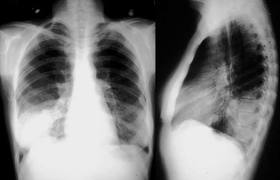

Relación entre los resultados de la radiografía de tórax y el inicio del tratamiento antibiótico en el tratamiento de la neumonía adquirida en la comunidad por médicos generales

En los pacientes con sospecha de neumonía adquirida en la comunidad (NAC), los médicos de cabecera tuvieron sistemáticamente en cuenta los resultados de las pruebas de respuesta positiva para iniciar el tratamiento antibiótico y tuvieron mucho menos en cuenta las pruebas de respuesta negativa. Estos resultados justifican la aclaración de qué se debe hacer en los casos de sospecha clínica de NAC sin confirmación radiológica. The Annals of Family Medicine, noviembre de 2024,